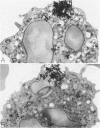

The morphology and function of cytoplasmic lipid bodies in human neutrophils were evaluated. By transmission electron microscopy, neutrophil lipid bodies were cytoplasmic inclusions, usually several microns in diameter, that occasionally coalesced to attain a diameter up to 7 microM. Neutrophil lipid bodies were not enveloped by membrane but were often surrounded by a more electron-dense shell at their periphery. Normal peripheral blood neutrophils contained an average of approximately one lipid body per cell. Lipid bodies appeared in greater numbers in neutrophils from inflammatory lesions. Perturbation of neutrophils during conventional methods of cell isolation and purification modestly increased lipid body numbers in neutrophils, whereas incubation of neutrophils with 1 microM oleic acid rapidly induced lipid body formation over 30 to 60 minutes. After granulocytes were incubated for 2 hours with 3H-fatty acids, including arachidonic, oleic, and palmitic acids, electron microscopic autoradiography demonstrated that lipid bodies represented the predominant intracellular sites of localization of each of the three 3H-fatty acids. There was lesser labeling noted in the perinuclear cisterna, but not in cell membranes. Virtually all of each of the three 3H-fatty acids incorporated by the neutrophils were esterified into chromatographically resolved classes of neutral lipids or phospholipids. These findings indicate that cytoplasmic lipid bodies are more prominent in neutrophils in vivo engaged in inflammatory responses and that these organelles in human neutrophils function as sites of deposition of esterified, incorporated fatty acids.